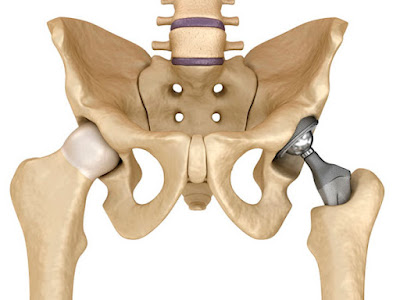

Prótesis de Cadera

Cirugía para reemplazar una cadera desgastada y recuperar la movilidad.